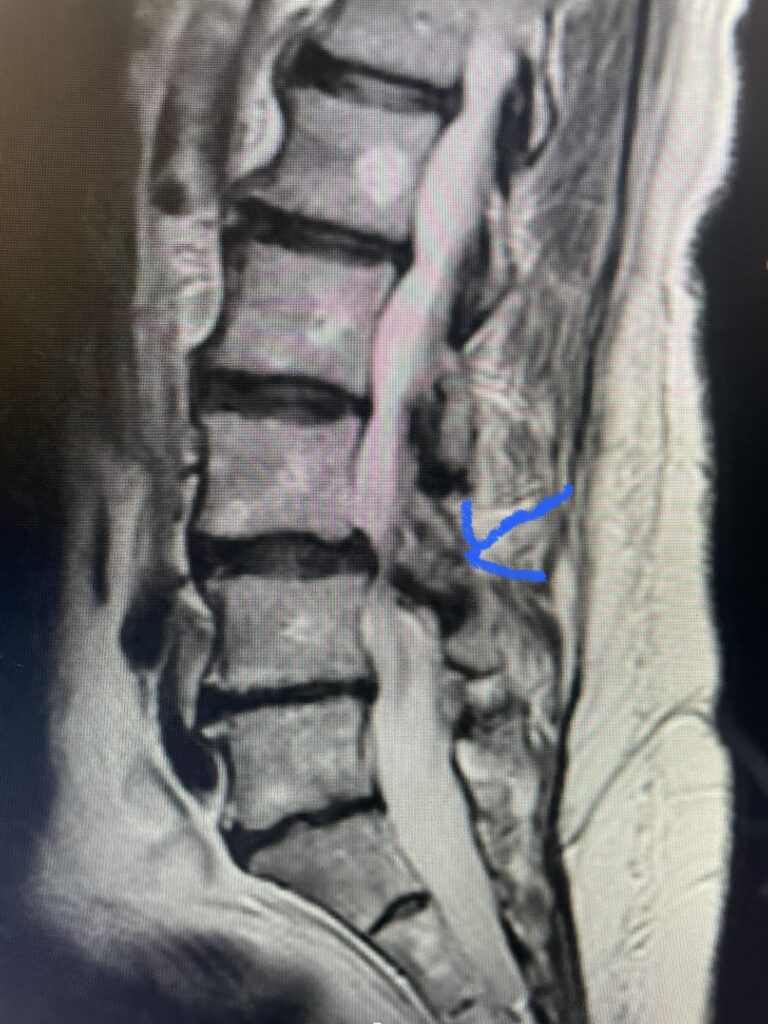

The actual structural cause of lumbar thecal sac compression can vary in degenerative spondylolisthesis and stenosis. The culprits are commonly thickened ligamentum flavum or severe facet […]